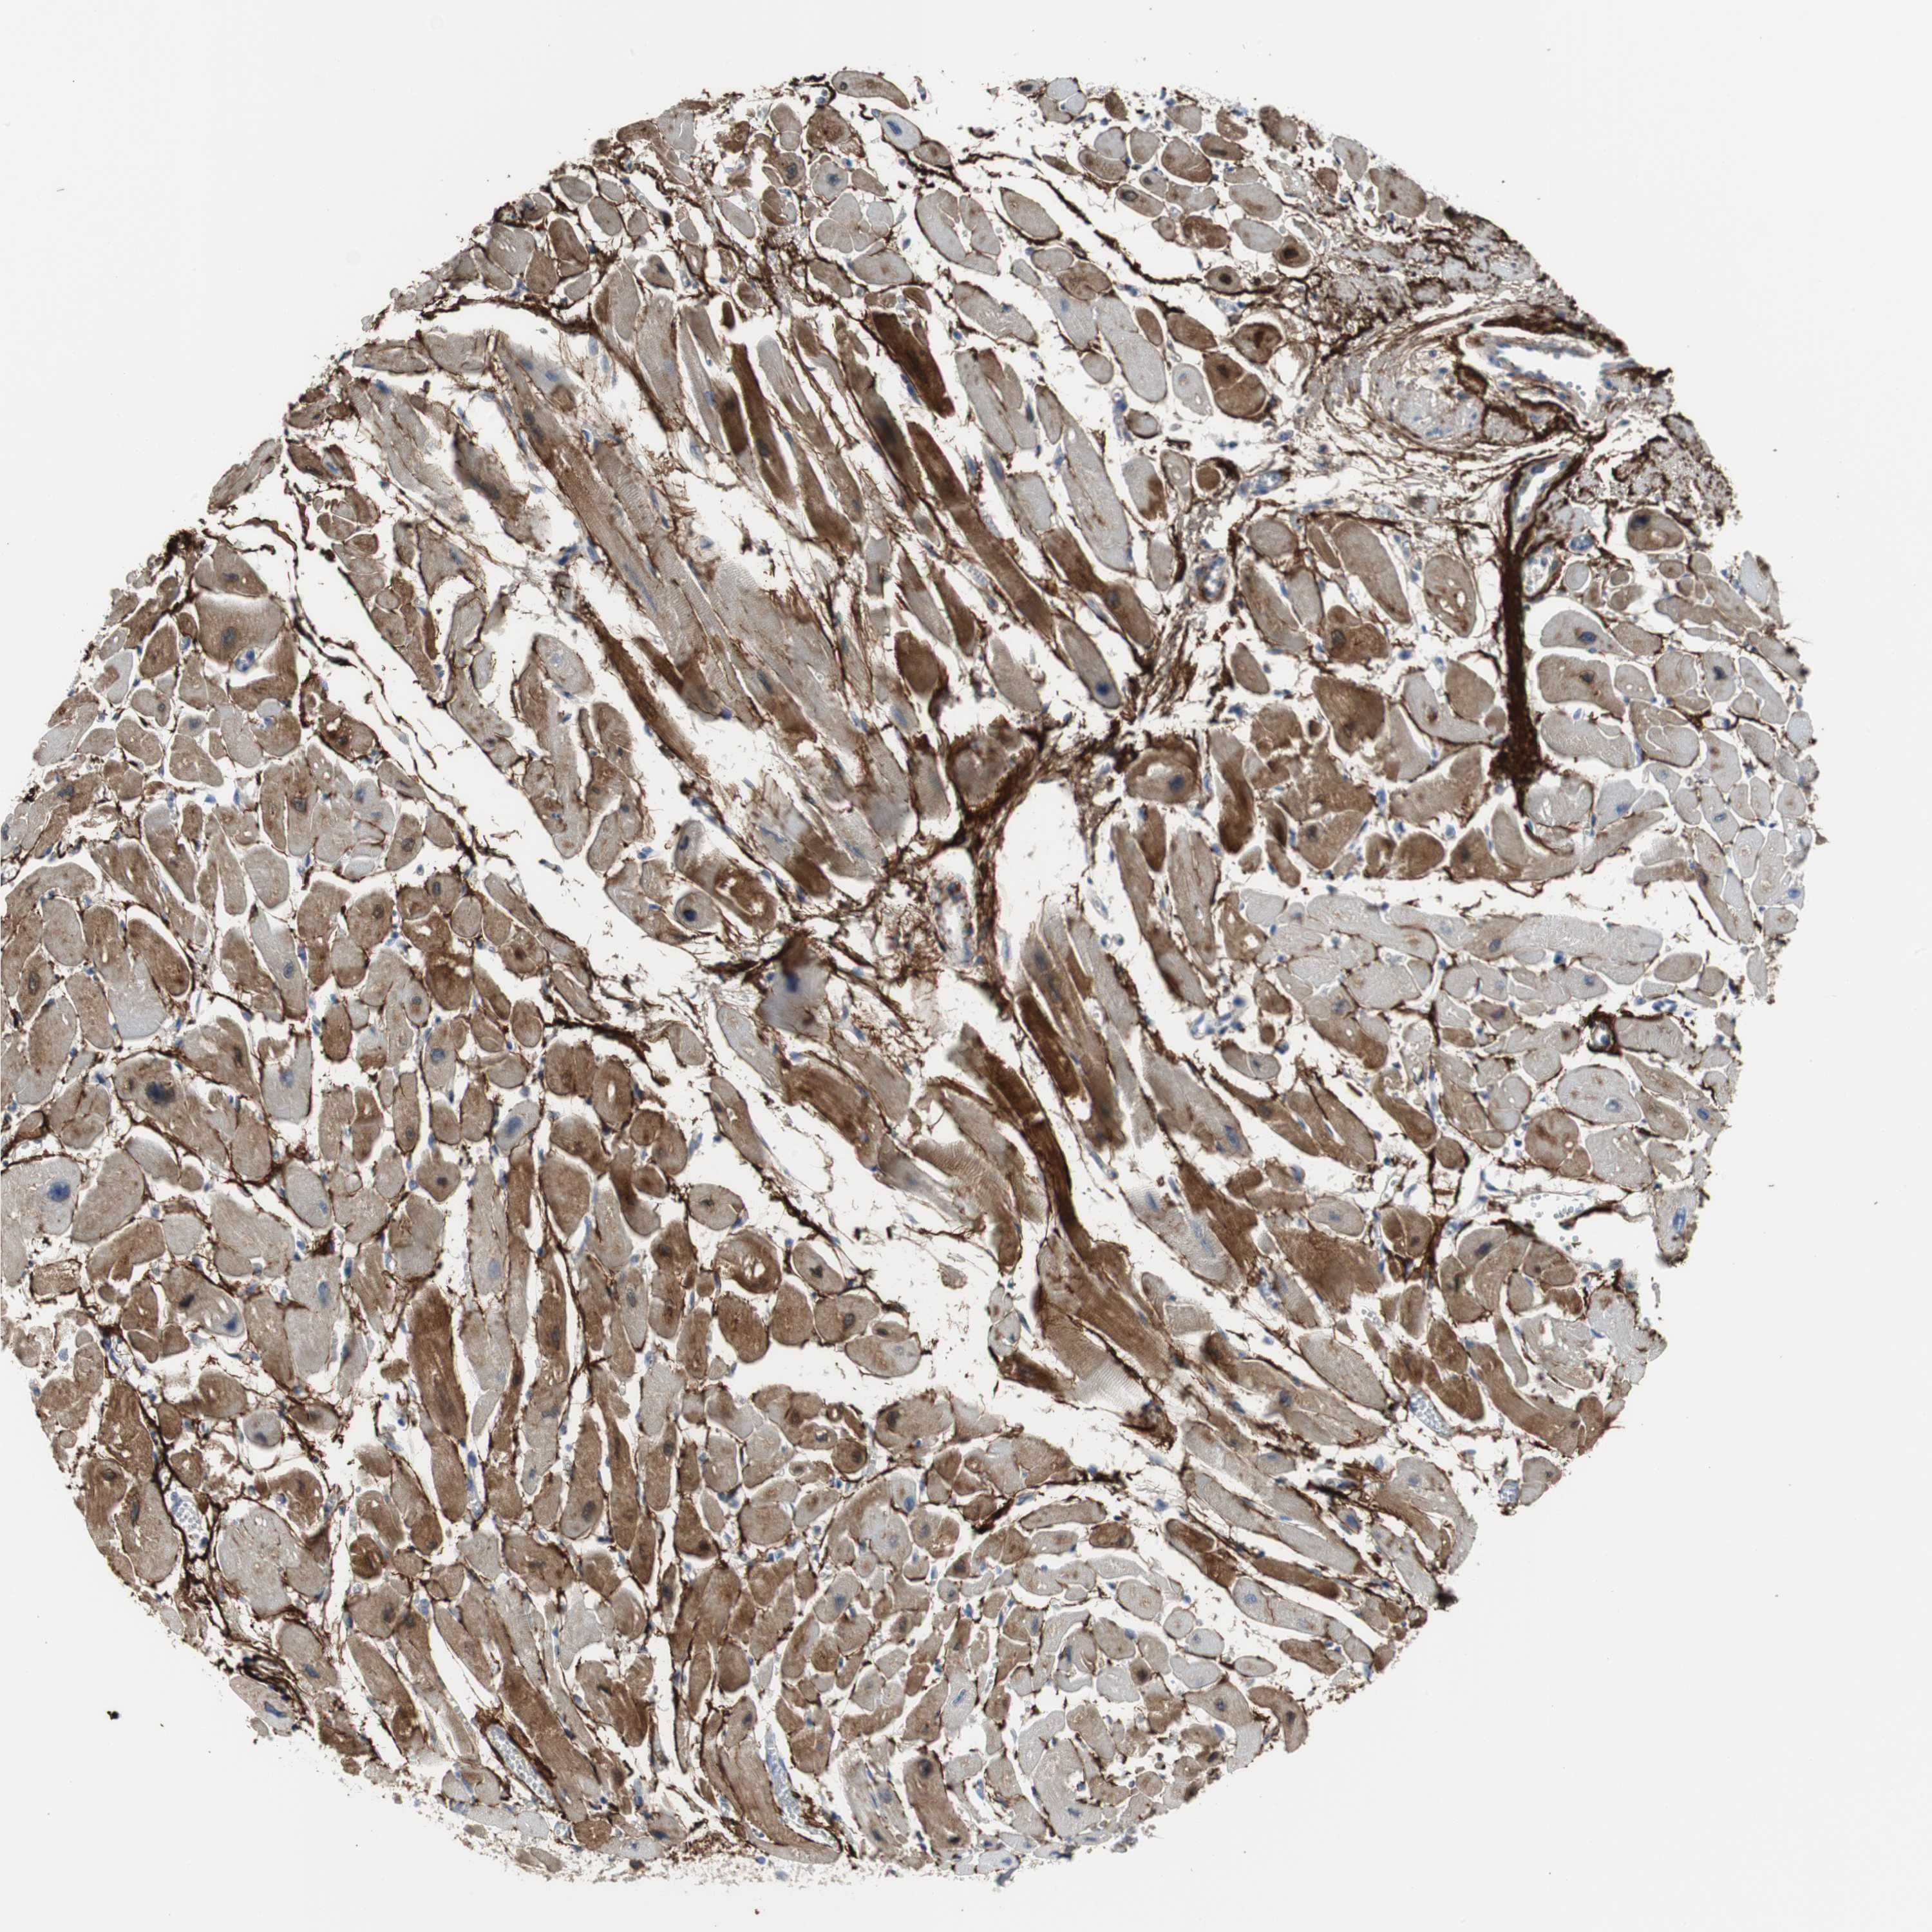

HEART MUSCLE - Antibody stainingi

Antibody staining in the annotated cell types in the current human tissue is reported as not detected, low, medium, or high, based on conventional immunohistochemistry profiling in selected tissues. This score is based on the combination of the staining intensity and fraction of stained cells.

Each image is clickable and will lead to virtual microscopy that enables deeper exploration of all samples and also displays staining intensity scores, fraction scores and subcellular localization as well as patient and tissue information for each sample.

Antibody HPA053294Antibody CAB007817

Cardiomyocytes Not detectedMedium